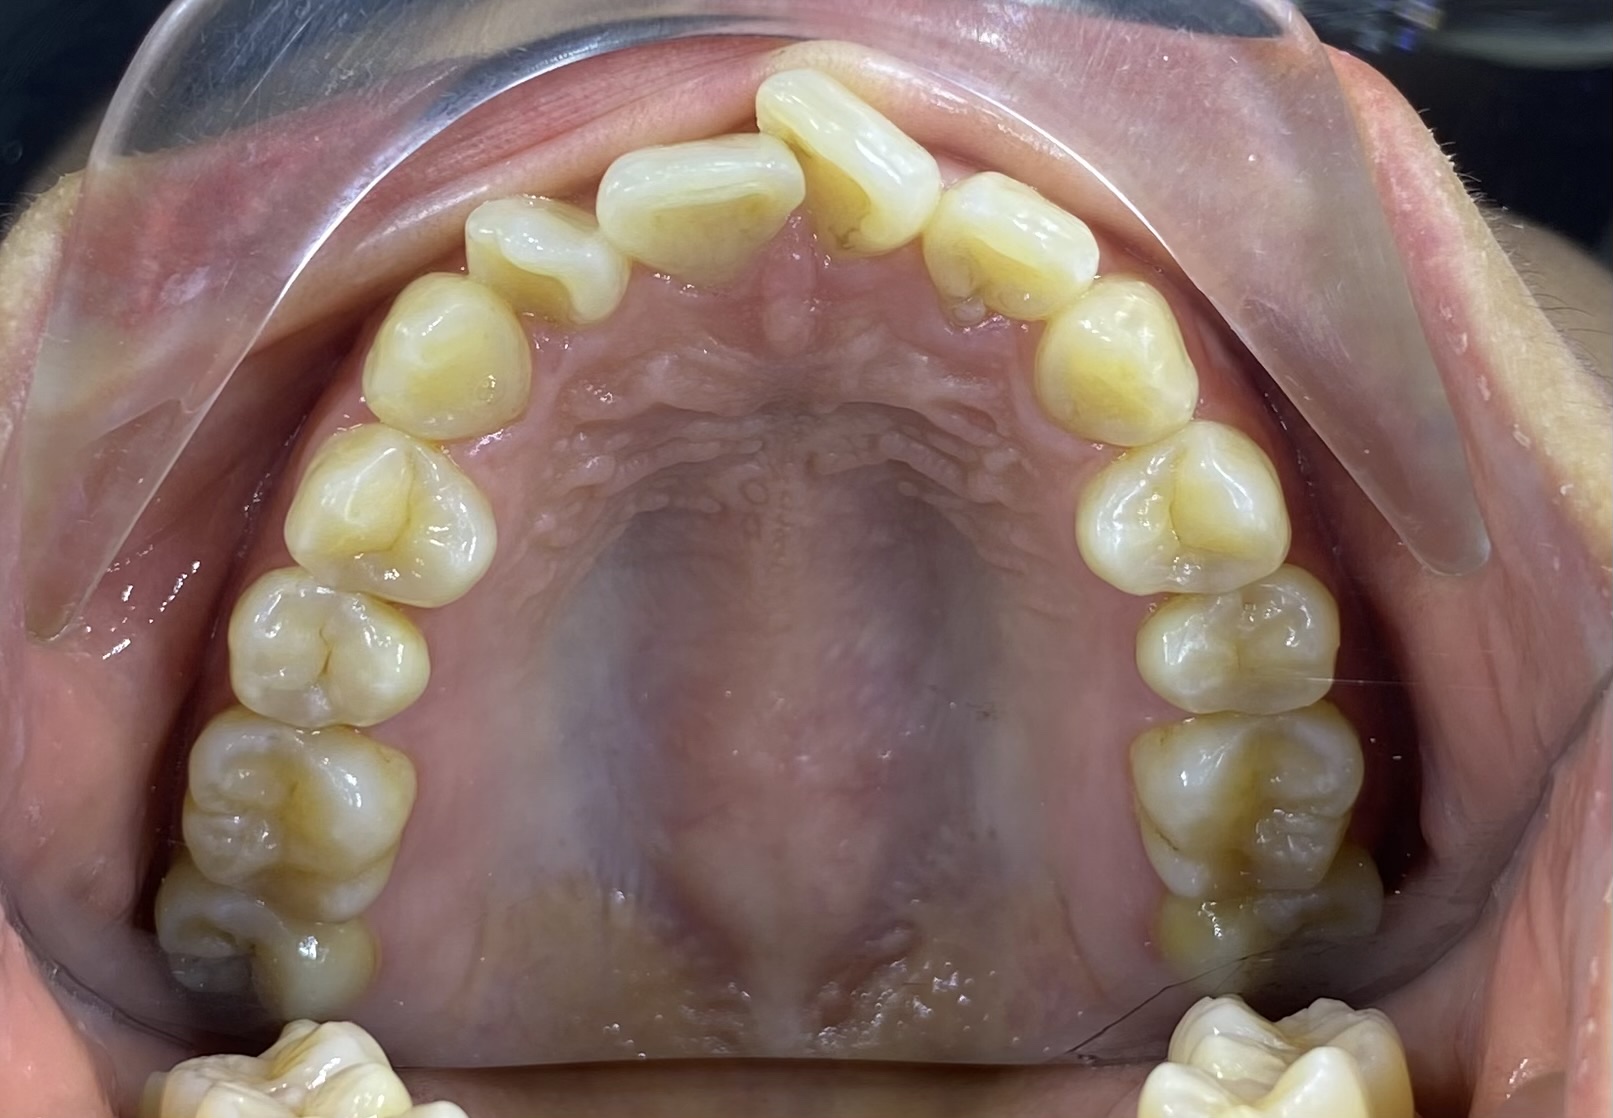

• Tình trạng răng ban đầu: Răng khấp khểnh, không đều,tình trạng hô nhẹ.